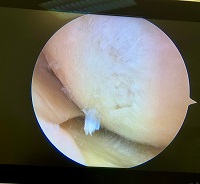

Dentro de la rodilla, la cápsula articular y los ligamentos cruzados posteriores y el anterior muy vascularizado ayudan a estabilizar la rodilla. Los meniscos medial y lateral son estructuras cartilaginosas intraarticulares sirven principalmente para absorber los golpes pero también proporcionan cierta estabilización. Ver más…